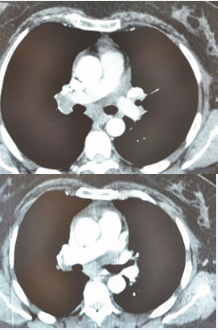

she was without fever during admission. No other physical abnormalities were observed. Laboratory investigations showed a white blood count 4600/mm3, C-reactive protein lower than 8mg/l, renal function indices were normal, a normal rate of liver enzyme. Tuberculosis skin test was 11 mm of in duration in diameter. Skin biopsy revealed granulomatous structures with central caseiting necrosis. A computed tomogram of the thorax disclosed mediastinal lymphadenopathy (Figure 2)

Figure 2 A comparison of regression of the size of mediastinal lymphadenopathy between 2017 and 2018.

and interstitial micro nodular densities. Broncho-alveolar lavage (BAL) with transbronchial needle aspiration was performed, direct smear microscopy examination of the sample and sputum for the presence of acid -resistant bacille by using Ziehl Neelson method was negative. However, the polymerase chain reaction (PCR) for M.Tuberculosis complex was not practiced. In the BAL, CD4+ lymphocytes and alveolar macrophages were predominantly. The ratio of CD4+ and CD8+ lymphocytes was over 2 (Figure 3).

Energy to tuberculin was found. In March 2018, another computed tomogram of the thorax was performed which showed a regression of the size of mediastinal lymphadenopathy in comparison to earlier scan. Cardiac echography revealed discreet pericarditis which disappeared after 2 months. Nasal mucosa biopsy was practiced and showed no specific inflammatory tissue without granulomatous structures and absence of necrosis or malignancy. The patient was referred to the ophthalmologist to search an ocular location of sarcoidosis.